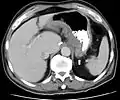

CT scan showing Crohn's disease in the fundus of the stomach

CT and MRI scans are useful for evaluating the small bowel with enteroclysis protocols.[138] They are also useful for looking for intra-abdominal complications of Crohn's disease, such as abscesses, small bowel obstructions, or fistulae.[139] Magnetic resonance imaging (MRI) is another option for imaging the small bowel as well as looking for complications, though it is more expensive and less readily available.[140] MRI techniques such as diffusion-weighted imaging and high-resolution imaging are more sensitive in detecting ulceration and inflammation compared to CT.[141][142]